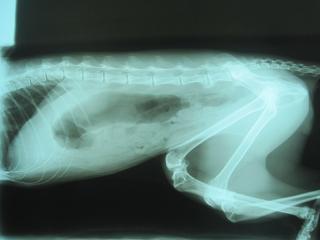

主題: 平溪張媽媽的2隻貓咪治療拉肚子 申請者姓名: 敏大哥 花色: 申請日期: 2012-07-01 21:56:37 申請者部落格: 申請者臉書網址: 所在縣市/合作醫院: 台北市/詠欣動物醫院 治療費用: 5200元 需求人數: 23人 已結案 (2012-12-01 21:24:18) 報名人員: Anita Yin(已付款)、Anita Yin(已付款)、Angel Kuo(已付款)、小可愛(已付款)、Hui-Yi Lo(已付款)、Mia Chang(已付款)、Milkbau Lu(已付款)、Sherry Fang(已付款)、Sherry Fang(已付款)、Juwan Liu(已付款)、冥王星獅子(已付款)、curry0(已付款)、Nina Chong(已付款)、Nicoletta Fon Fon(已付款)、Layla Hsu(已付款)、范立縈(已付款)、鳳姐(已付款)、Civie Szu Wei Shen(已付款)、Jakei Chia(已付款)、Jakei Chia(已付款)、Jakei Chia(已付款)、Shih Ju Chiu(已付款)、沙粒小貓(已付款)、 候補人員: 小舟、小舟、 動物病情說明: 貓咪這幾天吃不太下,其中鼻子白的金吉拉有血便,檢查出有梨型鞭毛蟲.治療幾天後,血便的金吉拉食慾仍不好.再幫他驗血 照x光.確認無其他問題.大腸有明顯發炎.則繼續吃藥 飲食控制.